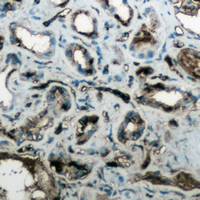

IHC (Immunohiostchemistry)

(Immunohistochemical analysis of Aquaporin 4 staining in human lung cancer formalin fixed paraffin embedded tissue section. The section was pre-treated using heat mediated antigen retrieval with sodium citrate buffer (pH 6.0). The section was then incubated with the antibody at room temperature and detected using an HRP conjugated compact polymer system. DAB was used as the chromogen. The section was then counterstained with haematoxylin and mounted with DPX.)